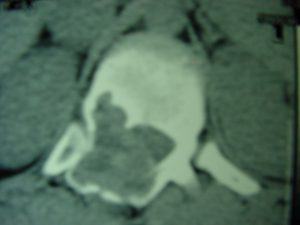

Εικ. 2: Προεγχειρητική αξονική τομογραφία του 12ου θωρακικού σπονδύλου (Εγκαρσια τομή)

Παρατηρείται ευμεγέθης εξεργασία στα οπίσθια στοιχεία του Θ12 σπονδύλου κυρίως δεξιά.